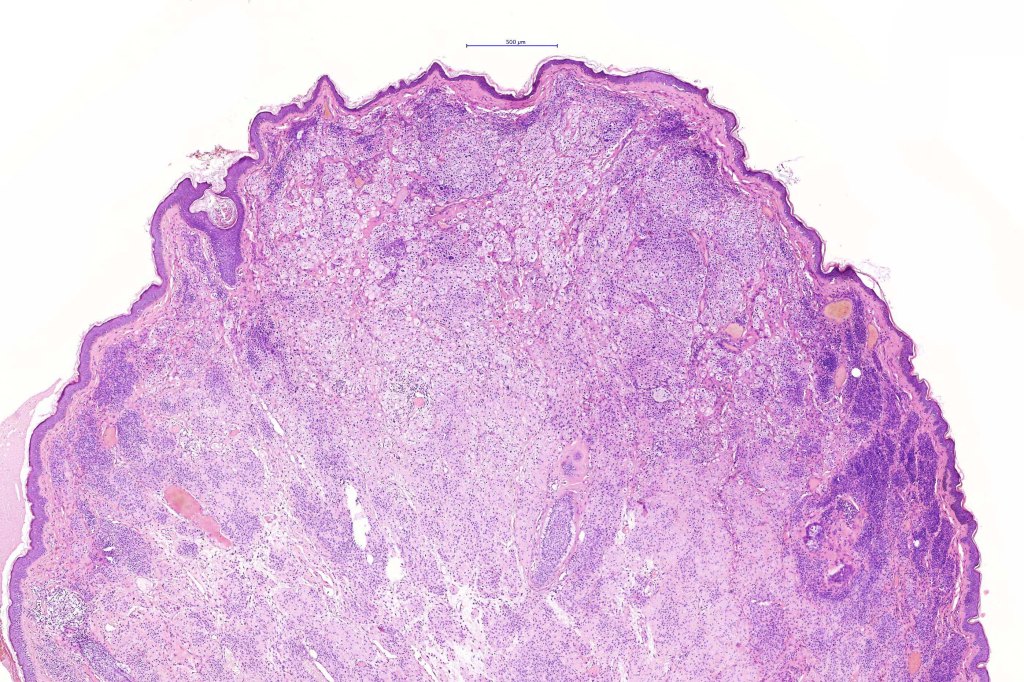

Balloon cell nevus represents the benign counterpart of balloon cell melanoma.

Histological features

.Balloon cell change is most often seen in banal melanocytic nevi but it has also rarely been described in cellular blue nevus, dysplastic nevus, combined nevus, halo nevus & Spitz nevus. Lesions with <50% of balloon cells are sometimes described as nevi with balloon cells. Nevi with >50% balloon cells are described as balloon cell nevus.